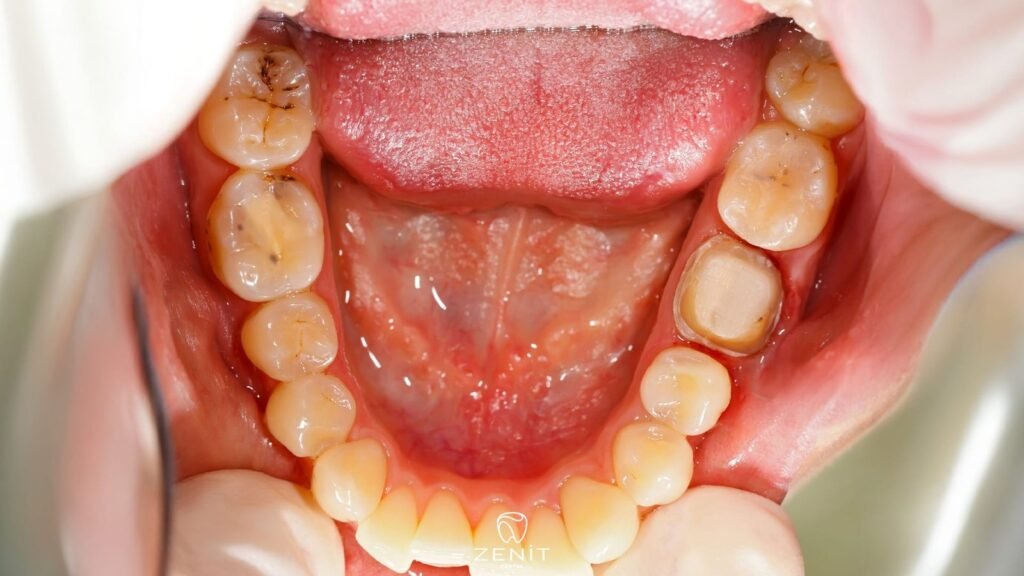

Zamanla bu bakteriler, ağız ortamında kalan şekerleri asitlere dönüştürür ve bu asitler diş minesini yavaşça aşındırır. Tıpkı bir kayanın üzerine damlayan su gibi, sabırla ve fark ettirmeden ilerler. Bir gün aynaya baktığında küçük bir siyah nokta görürsün ya da dişini ısırırken ani bir ağrı hissedersin. İşte o zaman “keşke biraz daha dikkat etseydim” demek için artık çok geç olabilir.

Ağızda bulunan bakteriler, yediğimiz yiyeceklerdeki şekeri kullanarak asit üretir. Bu asitler, ilk etapta diş yüzeyinde minik aşınmalara neden olur. Başlangıçta fark edilmez; ne ağrı vardır ne de belirgin bir leke… Ama bu sessiz süreç devam ettikçe, diş minesinin altındaki tabaka olan dentini de etkilemeye başlar. Dentin, mineye göre çok daha hassastır. İşte o noktadan sonra işler değişir sıcak bir kahve içerken, soğuk bir suyla ağzını çalkalarken ya da tatlı bir şey yediğinde “ufak bir sızlama” hissedersin. O sızlama aslında dişinin yardım çığlığıdır.

Bu saldırılar zamanla diş minesinin içindeki mineralleri çözmeye başlar. Mine zayıflar, incelir ve sonunda o minik deliklerin adı konur: çürük.